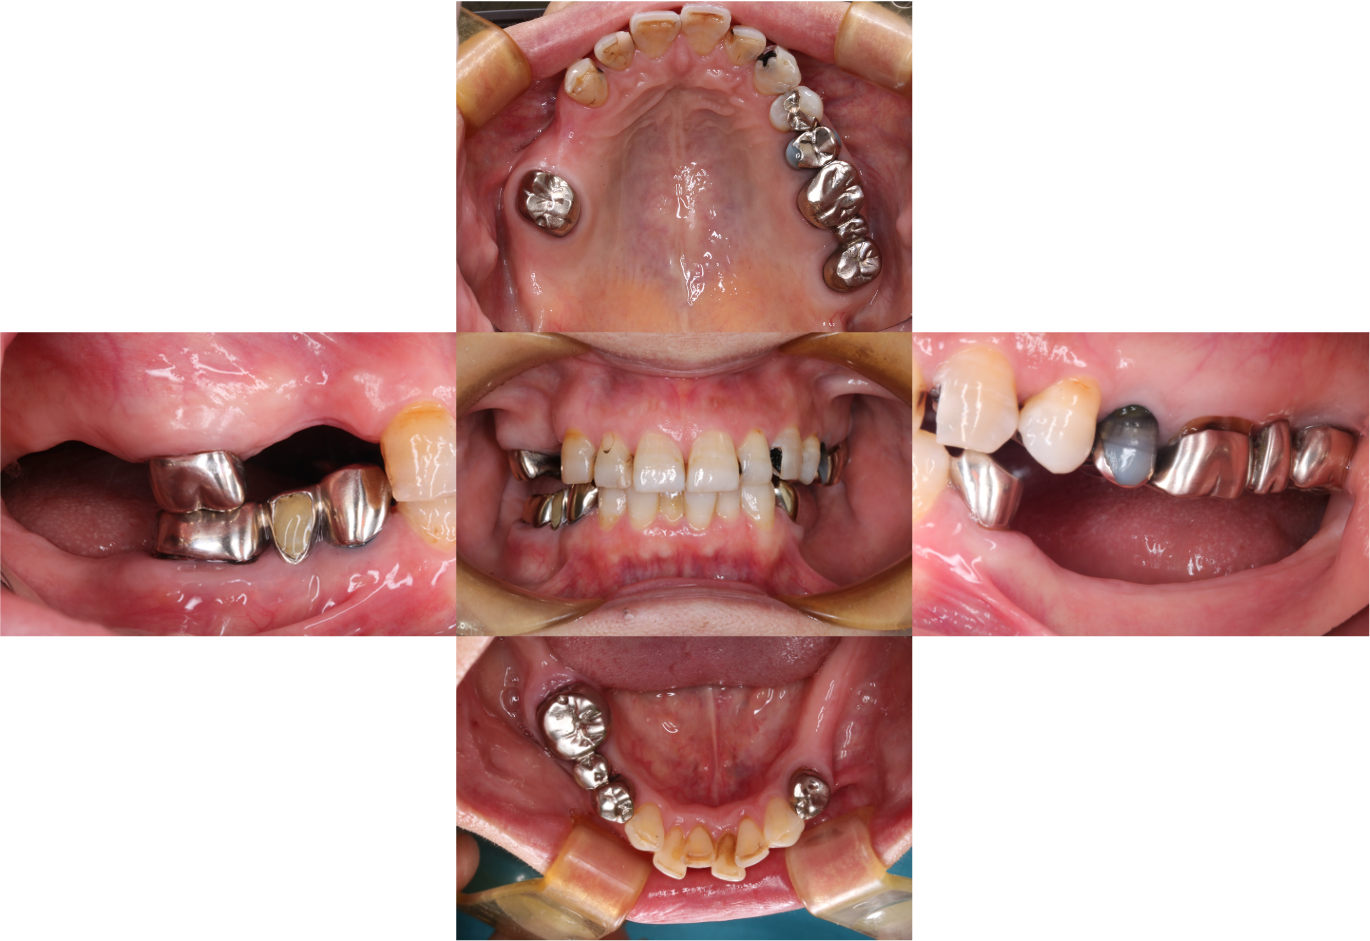

症例1

Before

.png)

After

患者さんの年齢/性別 | 女性/50歳代 |

主訴 | 奥歯でしっかりと食事が噛めない |

治療内容 | 左の奥歯は数年前に抜歯してから入れ歯を使用していて、右のブリッジとなっている奥歯で主に食事を噛んでいたとのこと。 |

治療期間/治療回数 | 5ヶ月/7回 |

費用 | CT 16,500円(税込) |

リスク・副作用 | 歯周病に感染・発症し重度に進行するとインプラントが抜けてしまうことがあります。また、手術後は数日間腫れが出る場合があります。 |